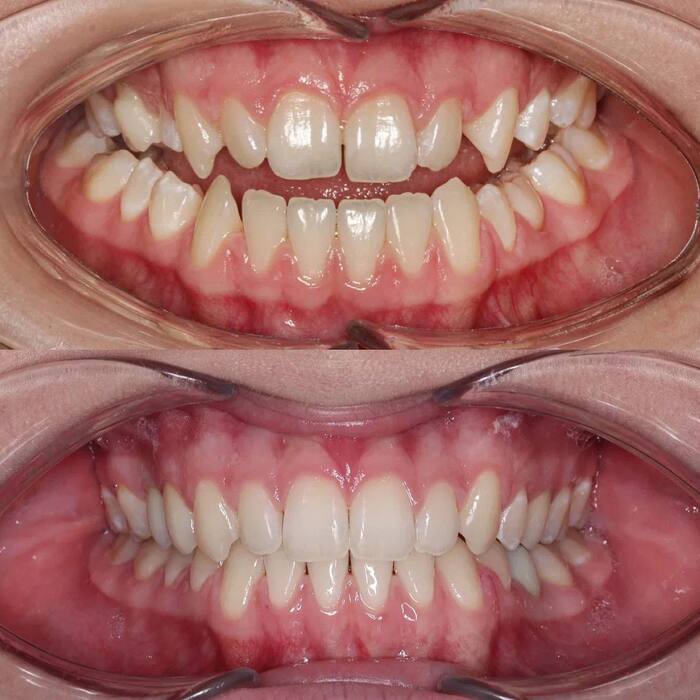

До или клиническая ситуация : нижние зубы перекрывают верхние (обратное перекрытие), наличие щелей между верхними и нижними зубами, несовпадение центров верхнего и нижнего зубных рядов, нарушение смыкания боковой группы зубов, кривизна резцов, практически полное отсутствие места для правого верхнего клыка.

Диагноз: мезиальный прикус, обратная резцовая окклюзия, трансверзальная резцовая окклюзия, дизокклюзия в области 1.3, 1.2, 2.2 и 2.3, перекрестная палатиноокклюзия в области боковой группы зубов, скученность и ретрузия резцов обеих челюстей.

Решение: дистализировать (смещать назад) весь нижний зубной ряд целиком с опорой на два ортодонтических винта для нормализации смыкания боковой группы зубов. Увеличить наклон резцов верхней челюсти до нормальных значений для получения правильного перекрытия резцов в сагиттальной и вертикальной плоскостях. Использовать раскрывающую пружину для раскрытия места под правый верхний клык и сопоставления косметических центров верхнего и нижнего зубных рядов между собой. Расширить верхний зубной ряд для коррекции перекрестного прикуса в боковых отделах и добычи пространства для правого верхнего клыка.

Результат: получили физиологический прикус, нормализовали смыкание фронтальной группы зубов во всех плоскостях (сагиттальной, вертикальной и трансверзальной). Добились правильного смыкания зубов в боковых отделах. Расширили зубные ряды и нормализовали наклон резцов верхней челюсти.